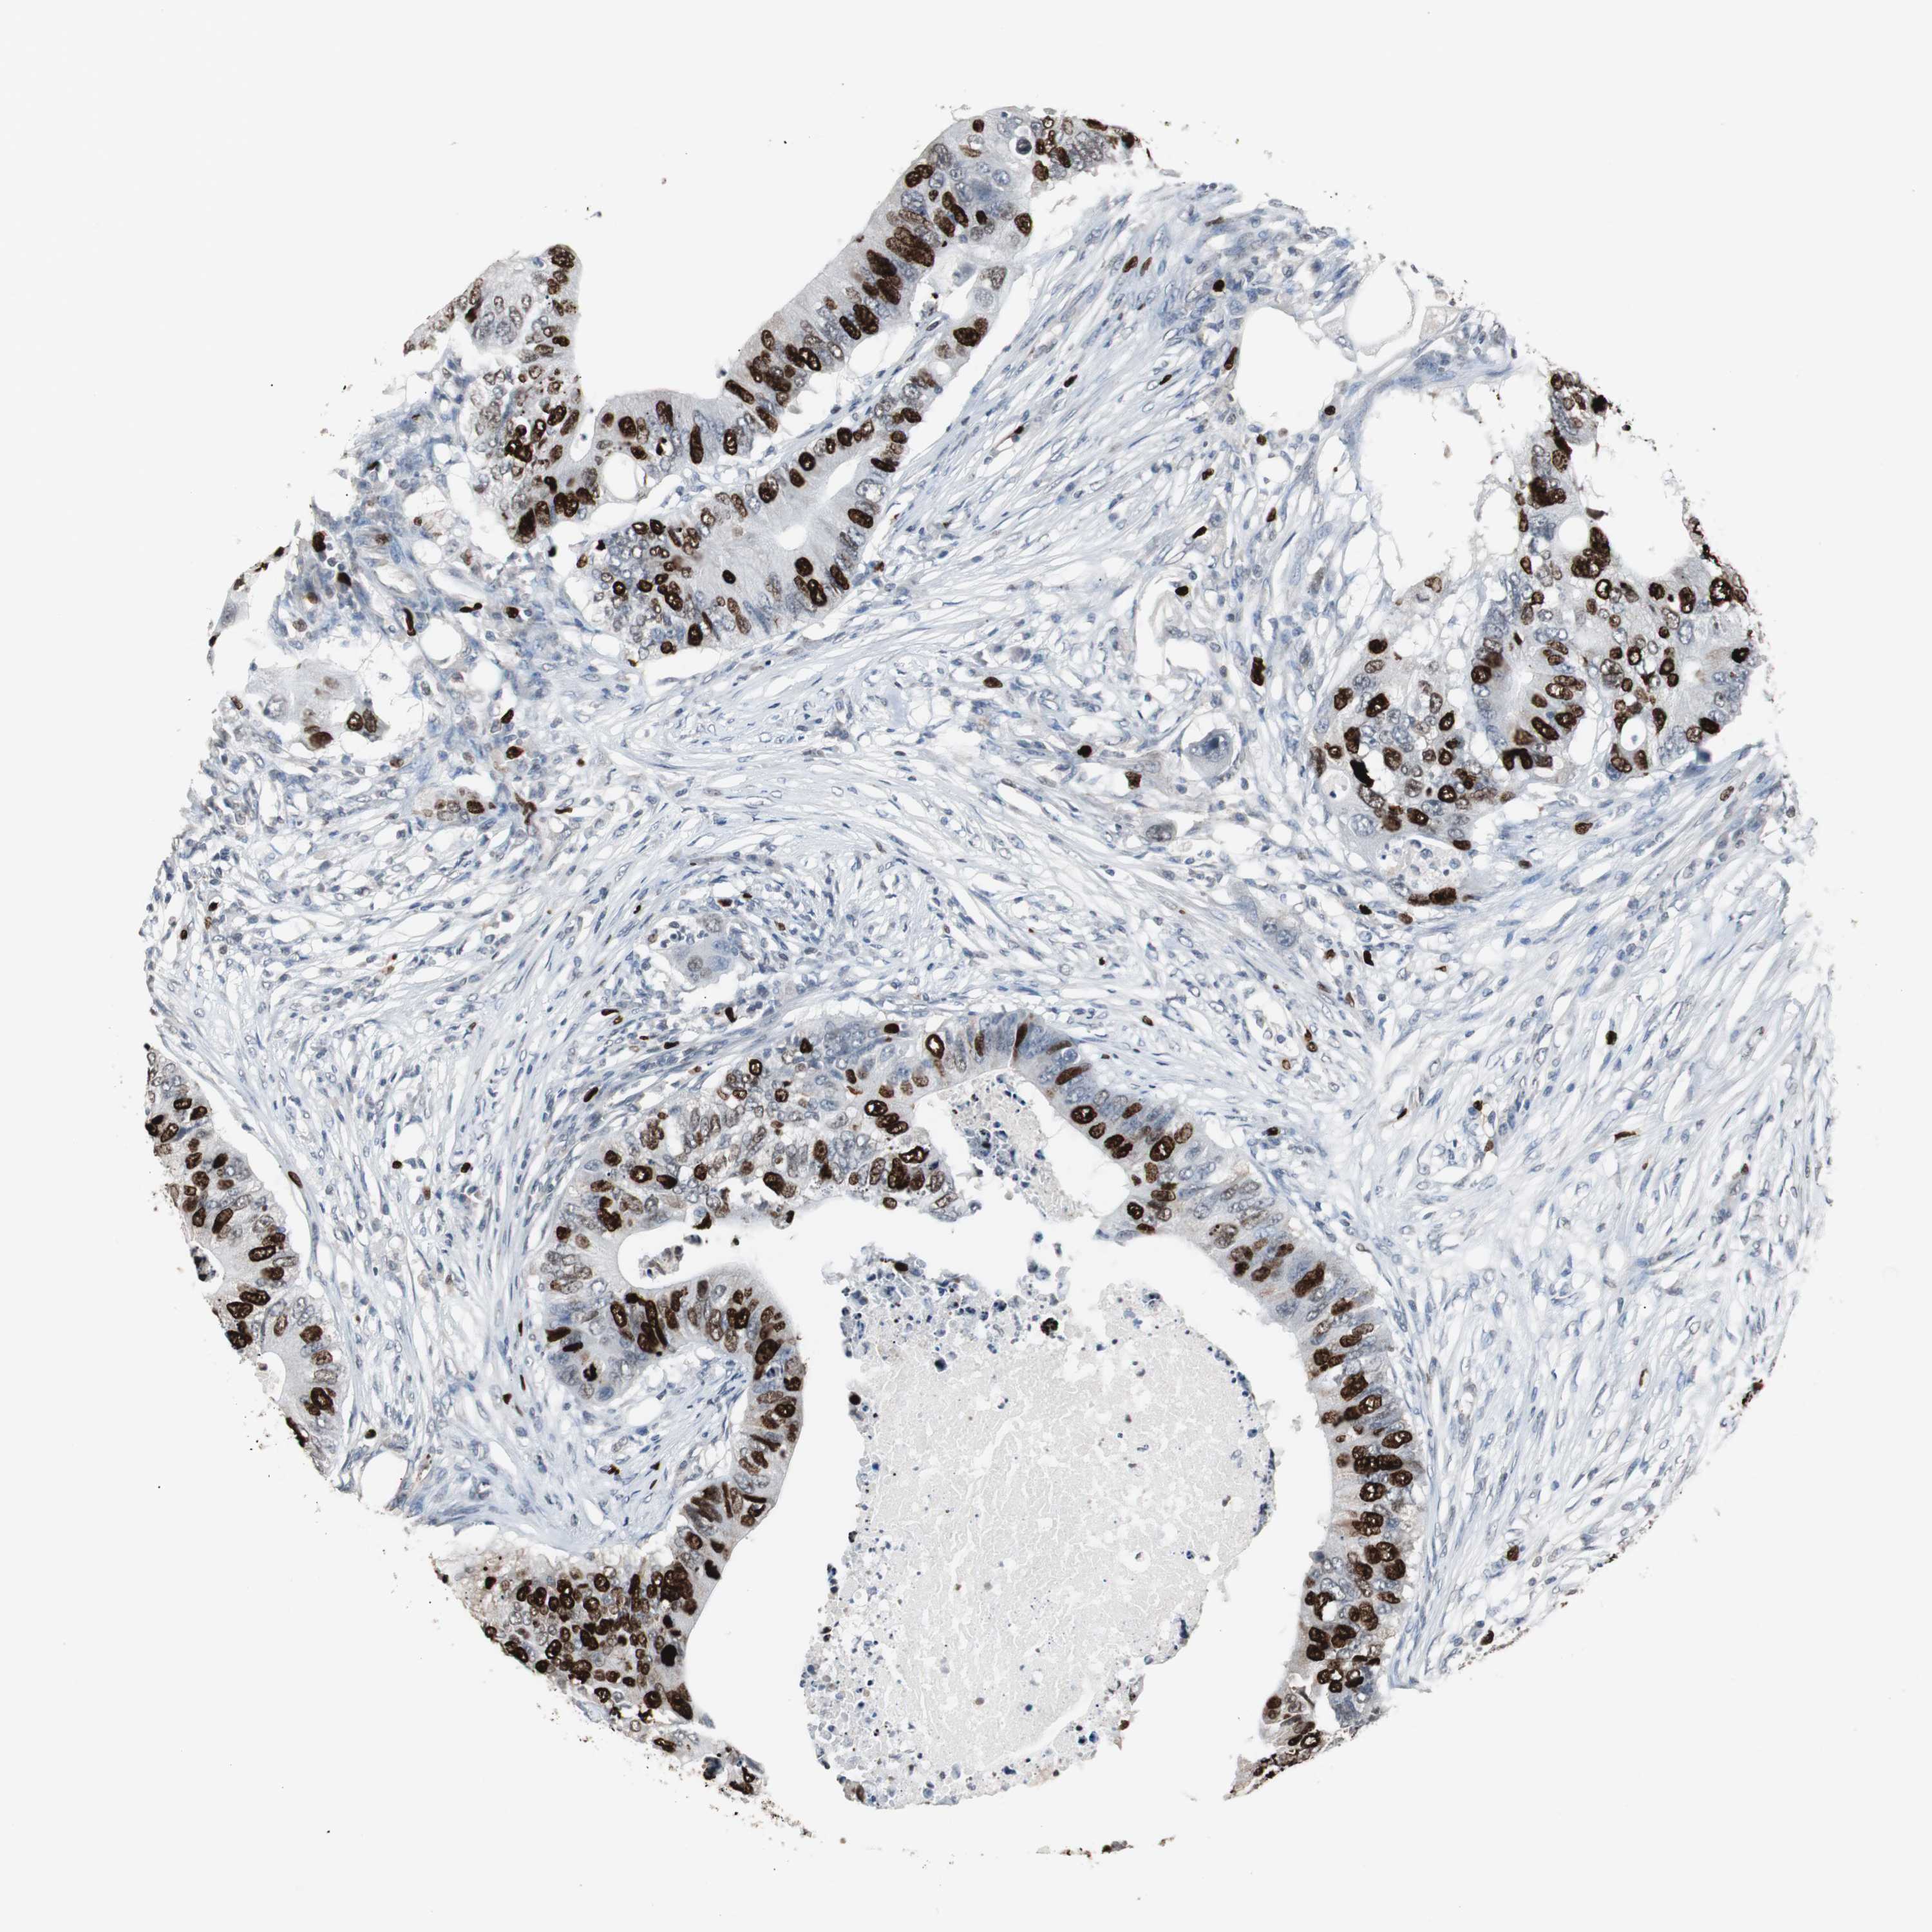

CANCER COLORECTAL CANCER Show tissue menu

Colorectal cancer

Human cancer

Colon adenocarcinoma